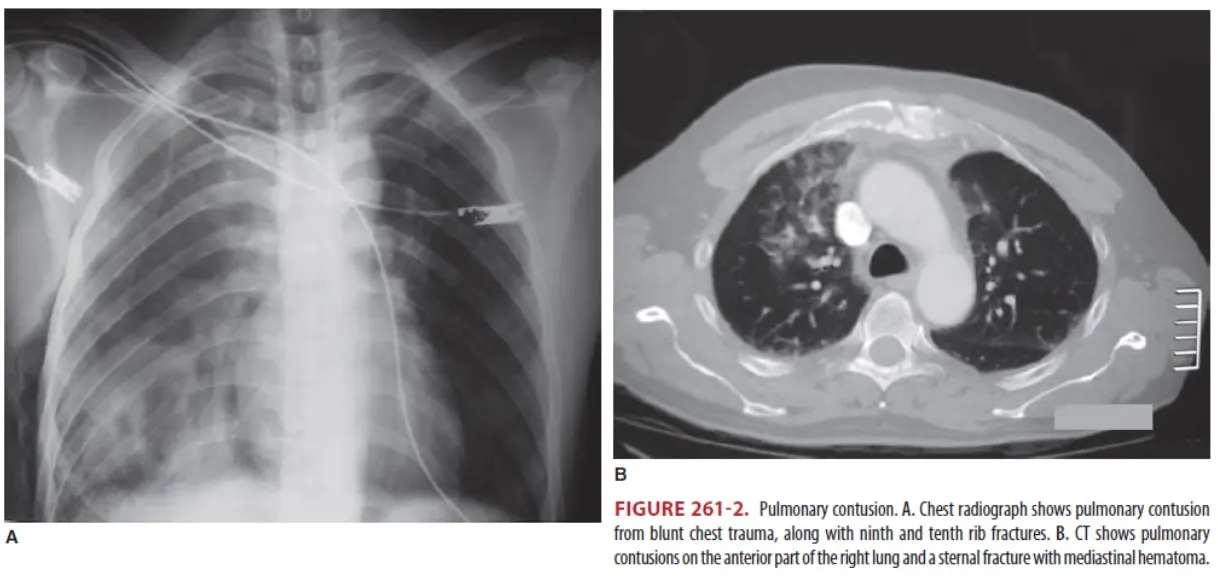

(2) Chest X-ray & CT

•

Mild or moderate contusion : Patchy, ground-glass opacities

Severe contusion : Widespread consolidation

Aspiration pneumonia 혹은 fat embolism과 비슷하게 보이나, 주로 12~24시간 후에 보이며

segmental distribution을 가지게 된다.